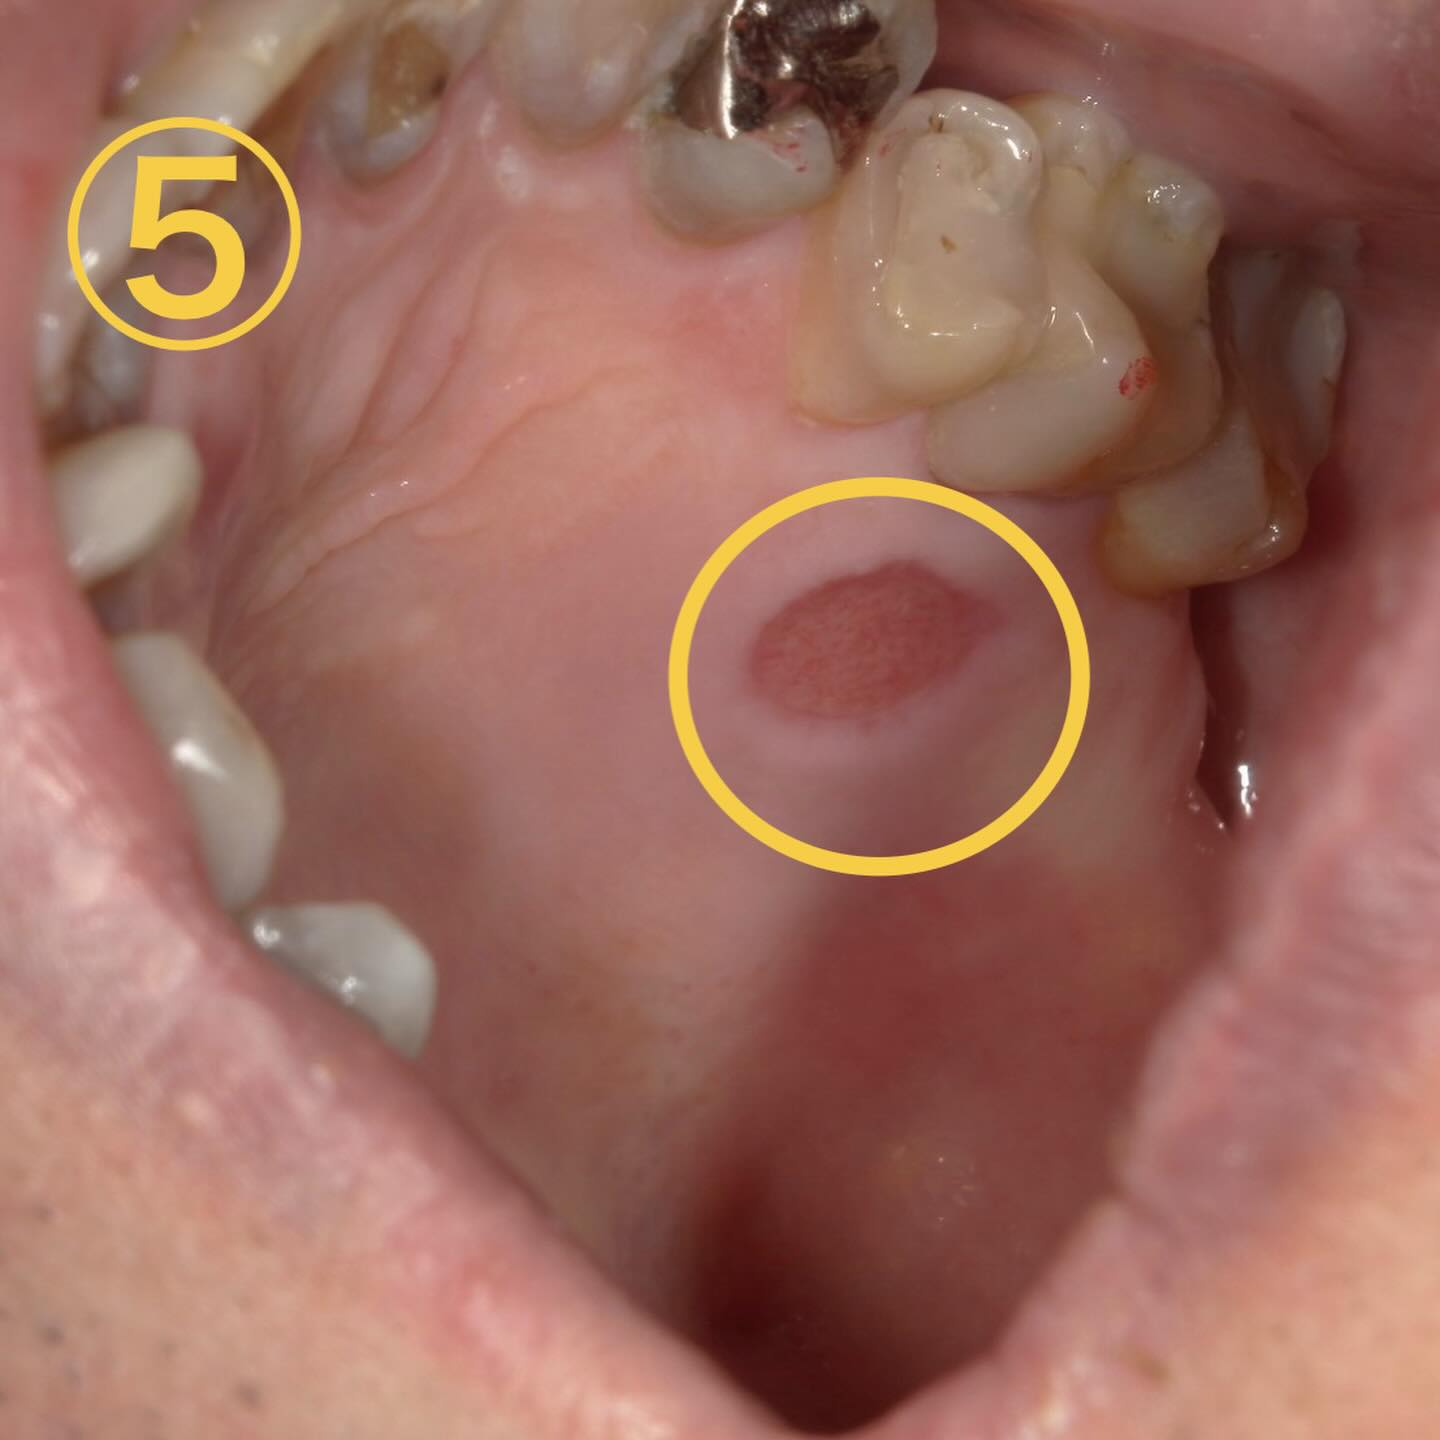

次に画像⑤です

これは口内炎ではありません🙅♀️

部位的にここは口蓋といって上顎の裏側になります✍️

これは火傷が原因なんです😫

最近は鍋物やお餅、おでんが原因で来院される方がとても多かったです⛄️

特徴→熱い物を食べた後に薄皮が剥がれた感じがする・ヒリヒリ痛い・沁みる

💊治療法→経過観察、気になるようなら含嗽薬